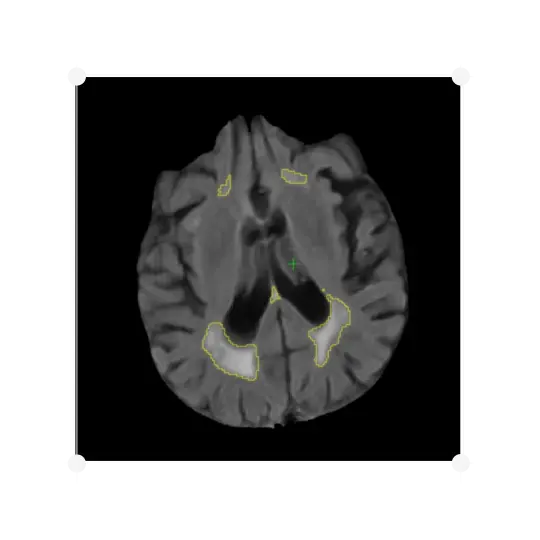

IXICO's automated analysis accurately quantifies the volume of WMH.

The identification of WMH is highly relevant to a dementia diagnosis, and is a criterion for the exclusion of subjects participating in a clinical trial, as well as a measure of treatment efficacy. IXICO provide a visual read to screen subjects with severe vascular pathology. IXICO can accurately quantify the volume of WMH using IXICO's automated methods, assessing a subject’s 3D T1W and FLAIR MR images.

IXICO's analysis delivers the volume of white matter, the volumes of hyperintense lesions, and the percentage of white matter hyperintensity. It can be applied to five regions of interest:

• Whole white matter

• Juxtaventricular

• Periventricular

• Deep white matter

• Juxtacortical

IXICO's method uses tissue classification and hyperintensity belief maps that are iteratively grown by analysing neighbouring voxels, and provides improved robustness to discriminate subjects with significant white matter pathology, with good correlation with Fazekas scoring and manual volumetry.